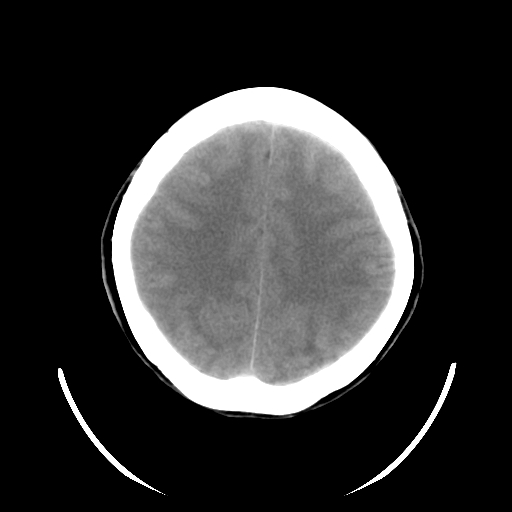

标题: CT19189:女,38岁,右侧肢体偏瘫、失语5天。 [打印本页]

女,38岁,右侧肢体偏瘫、失语5天,发病1小时曾在外院做头颅ct检查未见异常。

左侧基底节区、顶叶出血性脑梗塞,建议增强扫描或做cta检查,协助定性。

结合病史,考虑出血性脑梗塞.

左颞外囊区高密度病灶,周边脑白质指状水肿,低密度区不累及皮质,考虑是左外囊出血并脑水肿 。

结合病史,考虑出血性脑梗塞。------有无心脏病【风心】。请结合临床及进一步检查

考虑肿瘤性脑出血(胶质母细胞瘤)伴灶周水肿可能性大。38岁人暂不考虑出血性脑梗塞。